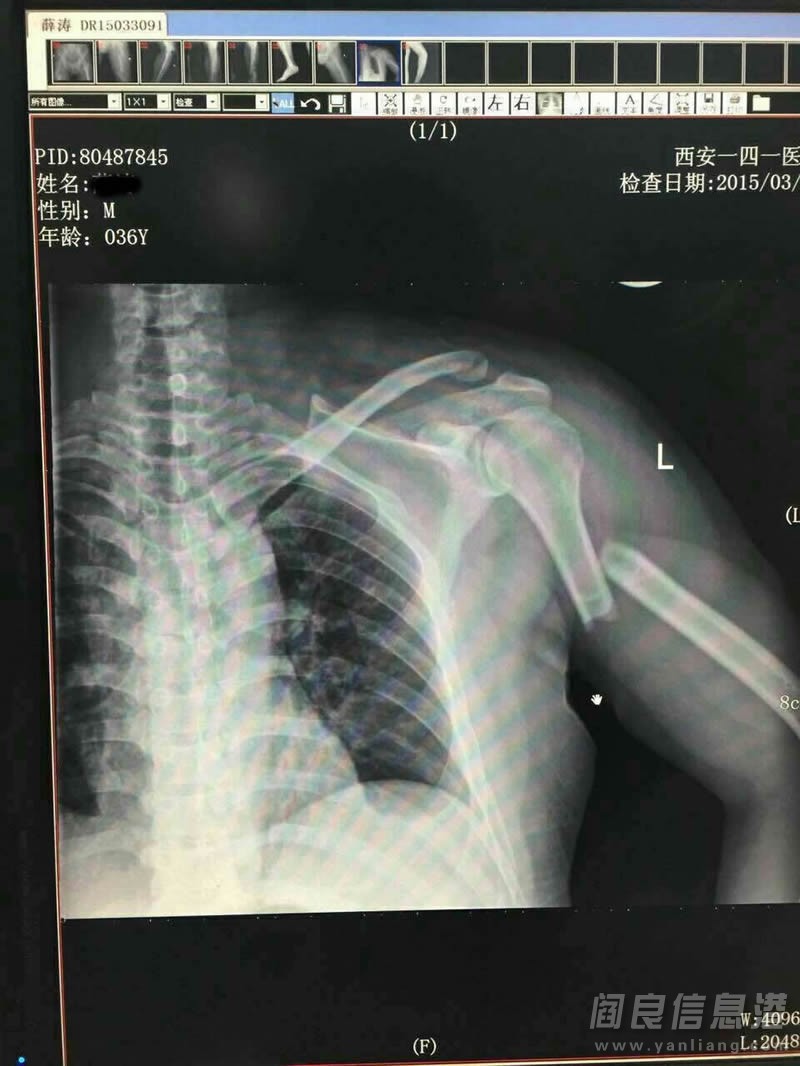

3.25宝马被撞当事人脾脏已经摘除,全身多处严重性骨折